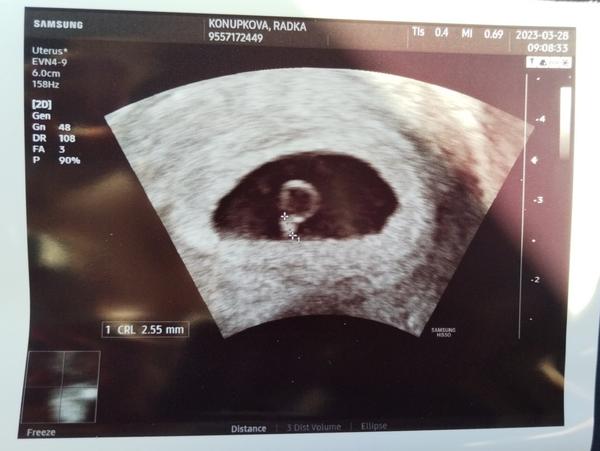

Holky tak jsme po kontrole,už máme 2,2 cm 😍🤣🤣 zahlédnuty mini ručičky, nožičky a hlavně srdíčko co bouchá😍😍 tatínek drobka z obrázků dojatý😉😉průkazku nemáme,ale PN díky rizikové práci a mému omdlívání vystavena, tak mohu být v klídku.Po Velikonočním pondělí náběry a pomalu se rozjede první screening,20.4.další ulltrazvuk😍Průkazku dostaneme až příště